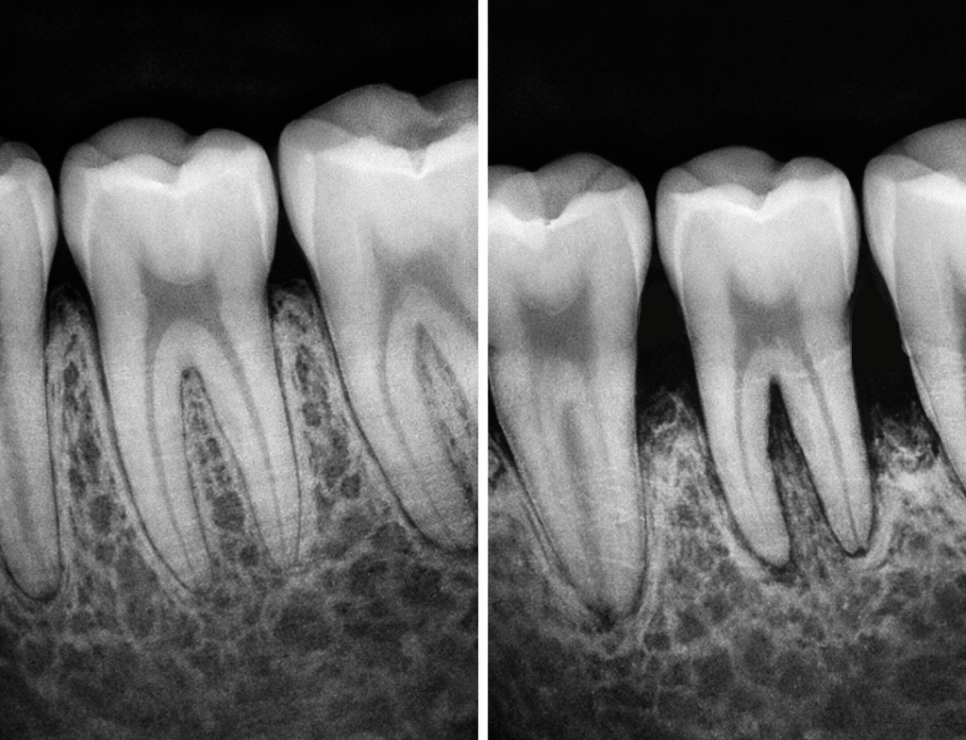

골량: 임플란트 나사가 들어갔을 때

사방을 튼튼하게 감싸줄

뼈의 양이 충분해야 됩니다.

골밀도: 뼈가 너무 무르지 않고 단단해야

식립 즉시 강한 고정력을 얻을 수 있습니다.

만약 뼈가 부족하다면

즉시 식립과 동시에 뼈 이식을

병행하기도 합니다.